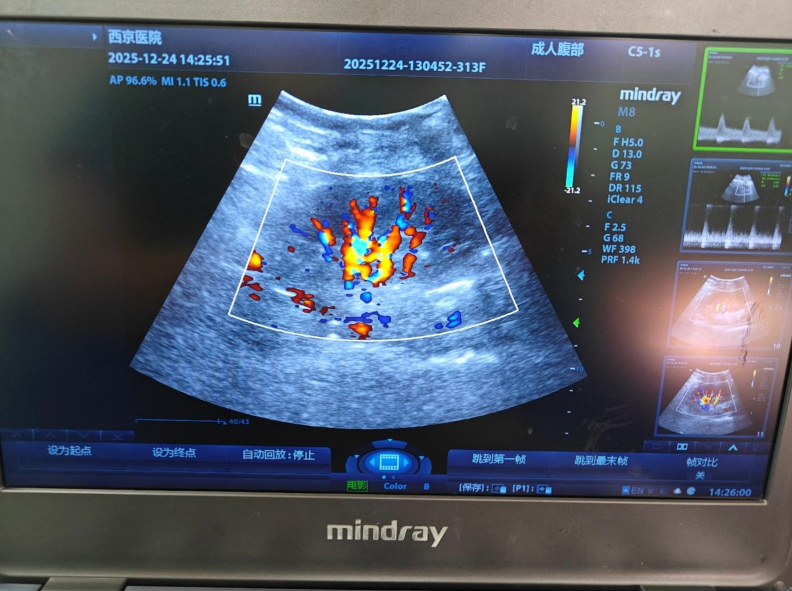

“只要能救他,我什么都愿意做。”王女士的坚定给了医护团队莫大的信心。西京医院肾移植团队迅速启动ABO血型不相容亲体肾移植专项诊疗方案,针对患者情况制定了个体化的术前免疫抑制方案和手术计划。经过严谨的术前评估、周密的准备以及高效的伦理审批流程,手术如期开展。术中,团队凭借丰富的临床经验和精湛的技术,精准完成血管吻合等关键操作,整个过程顺利流畅,开放血流后移植肾即刻恢复功能并产生尿液,见证了这场爱的奇迹。